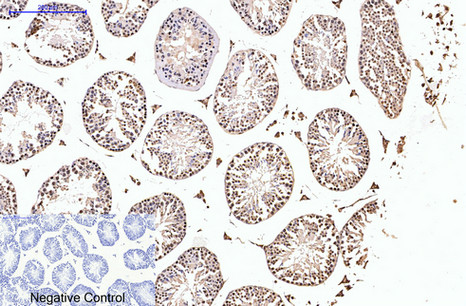

- Immunohistochemistry analysis of paraffin-embedded mouse testis tissue using PR antibody. High-pressure and temperature Sodium Citrate pH 6.0 was used for antigen retrieval. Negative control was used by secondary antibody only.